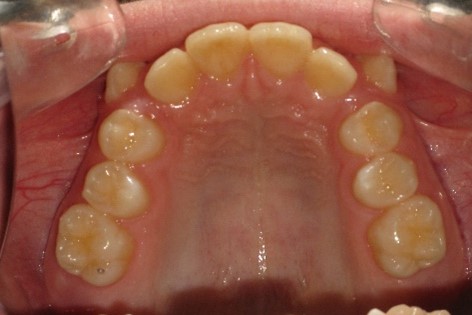

Рис.5. После дистализации с помощью аппарата Distal Jet.